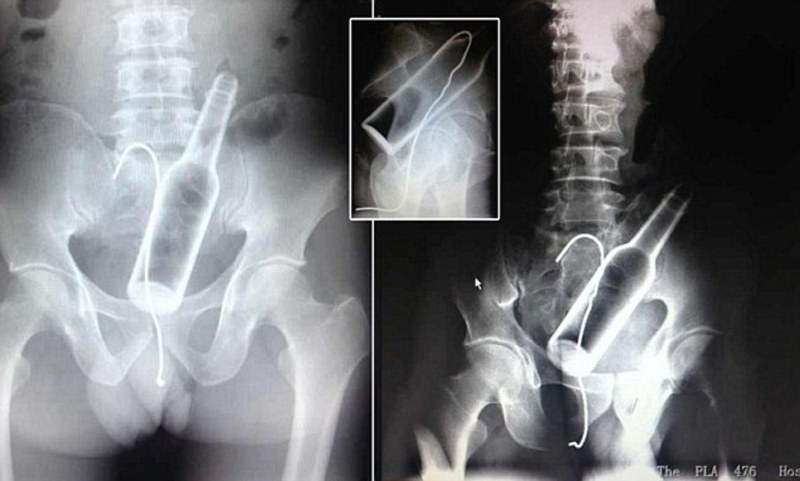

Anal hook suspension

Anus decoration suspension